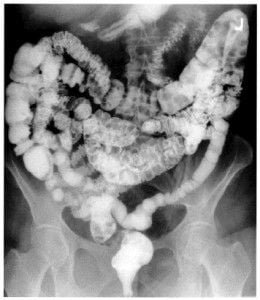

Abdomen, aparato digestivo y via biliarTécnicas de Exploración Radiológica Tránsito del intestino delgado Parte II 28 junio, 2012 Tidito Transito intestinal contraste simple Transito intestinal doble contraste yeyuno e ileon Patologia de Transito intestinal – Enfermedad celiaca Tumor maligno ileon terminalEnfermedad inflamatoria intestinal